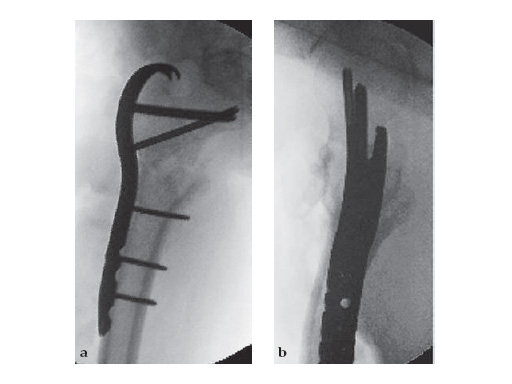

46-year-old female with an transverse intertrochanteric fracture

Case provided by Keith Mayo, Tacoma, USAHazards and labeling